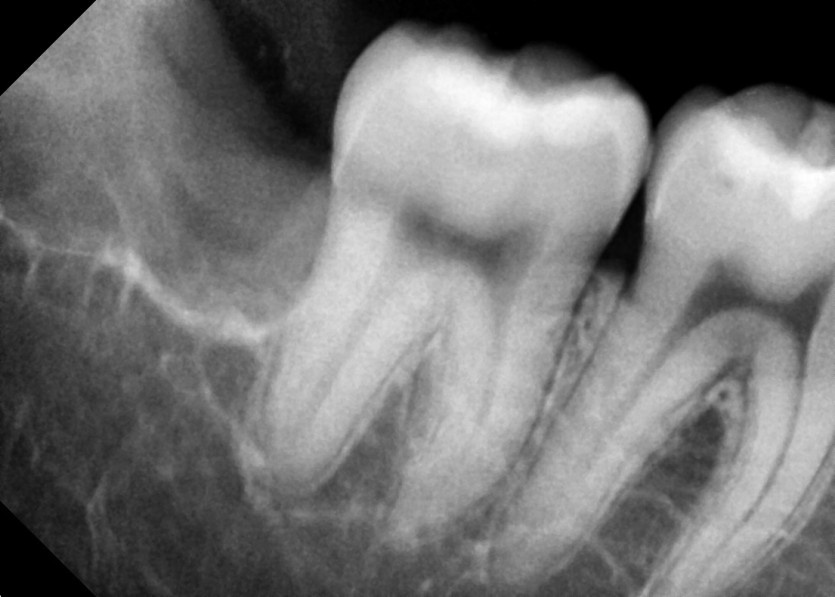

#18,48 사랑니 발치

구강 외과 전문의가 당일 발치했습니다.